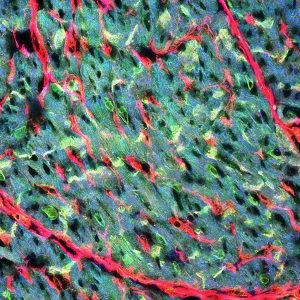

A cross-section of an adult mouse heart. Cardiac fibroblasts (red) can be found surrounding the muscle cells (green), which are connected by intercalated discs (yellow). The spatial arrangement of the cells facilitates coordination and communication between these different cell types and plays important roles in cardiac development, responses to cardiac injury, and repair of cardiac tissue. Field width 0.21 mm. Image by Efrain Rivera Serrano. Research group: Dr. Barbara Sherry, Molecular Biomedical Sciences.